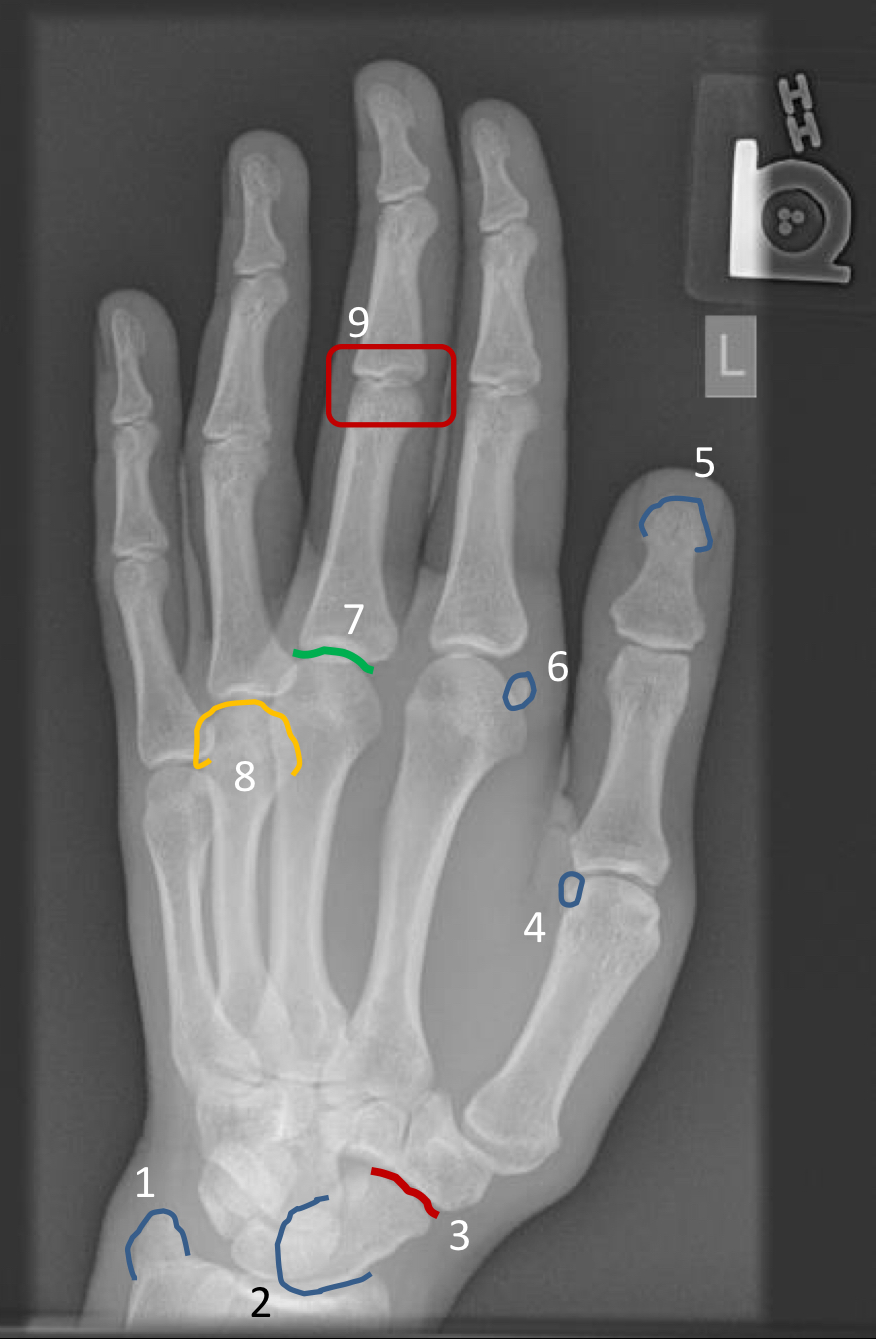

What view is this?

PA hand

purple arrow?

ungual tuft

1?

distal interphalangeal joint of the 2nd digit

2?

4th proximal interphalangeal joint

3?

head of 3rd metacarpal

4?

sesamoid of 2nd metacarpophalangeal joint

5?

base of 2nd metacarpal

6?

base of 1st proximal phalanx